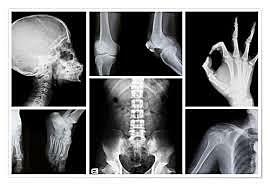

El radiodiagnóstico comprende el conjunto de procedimientos de visualización y exploración de la anatomía humana mediante imágenes y mapas. Algunas de estas aplicaciones son la obtención de radiografías mediante rayos X para identificar lesiones y enfermedades internas, el uso de radioisótopos en la tomografía computerizada para generar imágenes tridimensionales del cuerpo humano, la fluoroscopia y la radiología intervencionista.